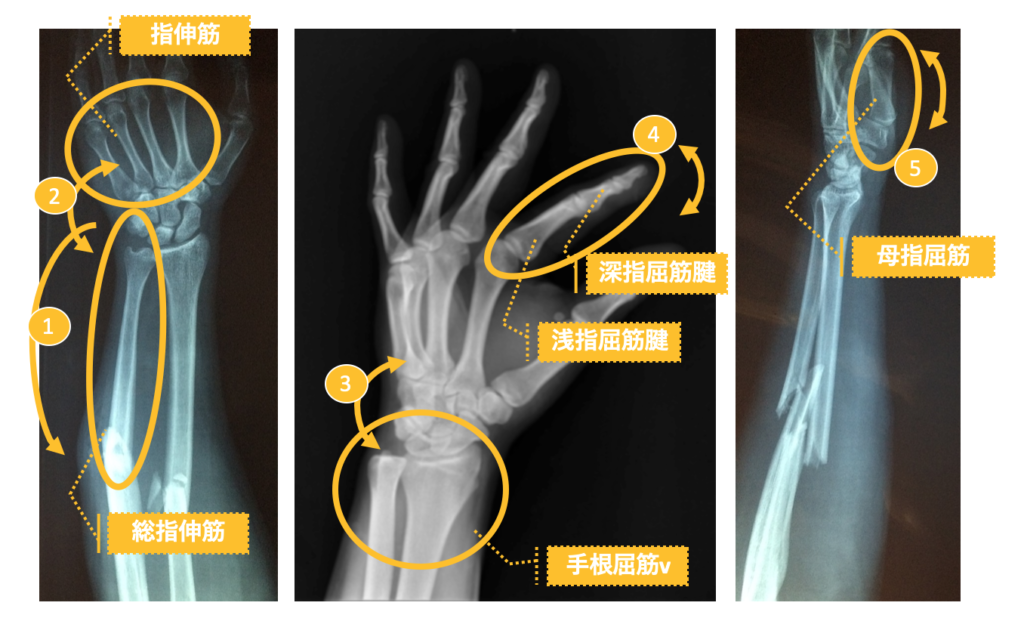

とはいえ、痛みの原因になる理屈や原理は同じです。筋肉や筋の仕組みを理解し、姿勢や体勢を意識することで、腱鞘炎になるリスクを回避することはできます。関節や周りの筋肉をイメージしやすい骨の写真を見ながら確認していきましょう。

どれも左腕の、左側が前腕(肘より先)、真ん中は手首と手のひら、そして右側は前腕を内側(親指側)を映したものです。うっすら影のように映っている形が筋肉を包む皮膚、腕の形です。

関節と筋肉をつなぐ腱の伝達構造:

①前腕の総指伸筋:腕の筋肉を最も意識しやすい部位。小指を動かした時に腕の外側の筋肉が張る箇所一帯に広がります。

②指屈筋:指を動かし際にヒクヒク動く筋肉。あまり使わない小指が特に弱く、短小指屈筋には無理がかかりやすい。

③手根屈筋:手首から腕への指2本分程度。バイクのエンジンをかけるような、手を持ち上げる動作で張りを認識できる。

④指屈筋腱:指の関節を繋ぐ腱であり、指の伸縮で緊張を認識できる。手の平側が浅指屈筋腱、指先側が深指屈筋腱。

⑤母指屈筋:親指のふっくらした箇所。親指の伸縮で筋肉の動きを認識でき、柔らかくすることで手が開くようになる。